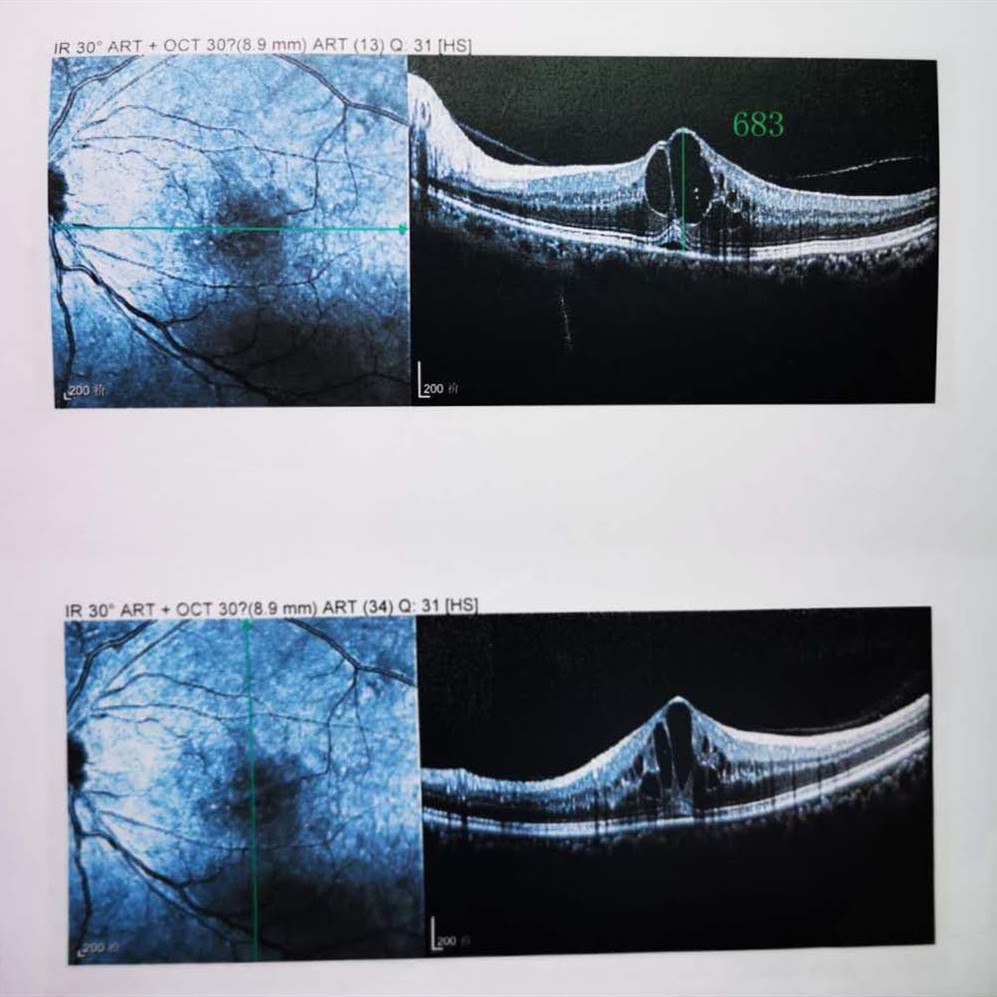

檢查結果顯示,武先生并沒有近視,右眼視力為1.0,但是左眼視力只有0.4,而且左眼視網膜各分支靜脈迂曲擴張,全網膜面見火焰狀出血,黃斑區(qū)高度水腫、滲出,黃斑中心凹厚度約683um。

OCT

(武先生初次就診眼底OCT檢查圖)

而正常的矯正視力是1.0,黃斑中心凹厚度在200um左右。

“你這黃斑都腫到正常人的三四倍大了!”廈門眼科中心吳國基院長醫(yī)生告訴武先生,“你這是左眼視網膜中央靜脈阻塞伴黃斑水腫,你左眼的視力下降、看東西變形,是因為你左眼視網膜的中央靜脈發(fā)生了阻塞、出血,導致眼底黃斑水腫了。”

那么,武先生的視力恢復情況如何呢?幸運的是,經過兩次玻璃體腔注藥術,武先生左眼的黃斑水腫得到明顯改善,視力已經恢復到0.8。

(武先生出院時眼底OCT檢查圖)